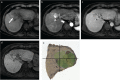

Gadolinium ethoxybenzyl diethylenetriamine pentaacetic acid (Gd-EOB-DTPA; Gadoxetic acid; Gadoxetate disodium) is a hepatocyte-specific MR contrast agent. It acts as an extracellular contrast agent in the early phase after intravenous injection, and then is taken up by hepatocytes later. Using this contrast agent, we can evaluate the hemodynamics of the liver and liver tumors, and can therefore improve the detection and characterization of hepatocellular carcinoma (HCC). Gd-EOB-DTPA helps in the more accurate detection of hypervascular HCC than by other agents. In addition, Gd-EOB-DTPA can detect hypovascular HCC, which is an early stage of the multi-stage carcinogenesis, with a low signal in the hepatobiliary phase. In addition to tumor detection and characterization, Gd-EOB-DTPA contrast-enhanced MR imaging can be applied for liver function evaluation and prognoses evaluation. Thus, Gd-EOB-DTPA plays an important role in the diagnosis of HCC. However, we have to employ optimal imaging techniques to improve the diagnostic ability. In this review, we aimed to discuss the characteristics of the contrast media, optimal imaging techniques, diagnosis, and applications.